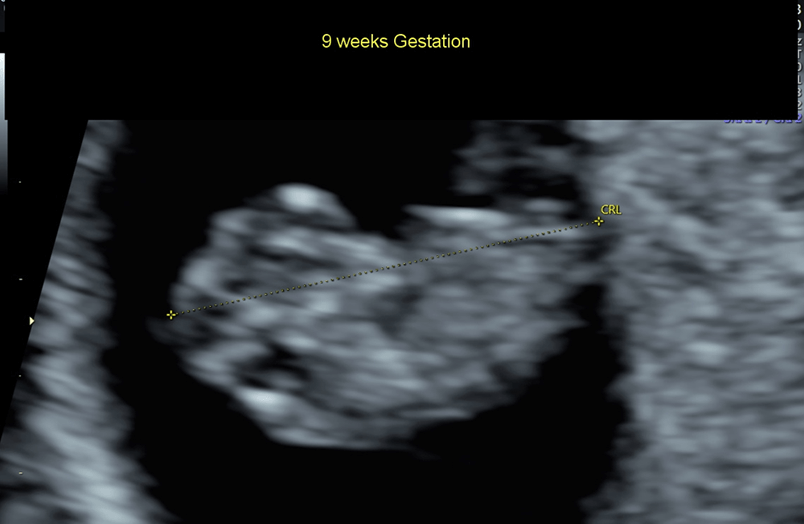

Your baby is now the size of a kumquat.

Baby is the size of Prune

Approx Baby Weight: 4g

Approx Baby Size: 3.1 cm

The baby's hands and feet are clearly visible.